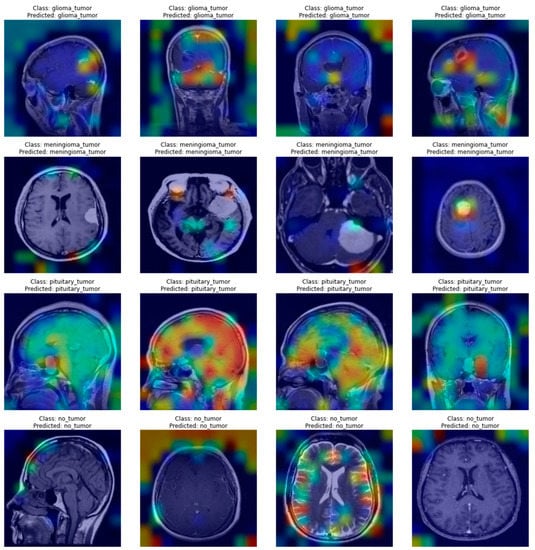

In the case of this research, explaining the decisions of neural networks is even more important than the raw scores the models achieved. It not only provides insights that allow us to assess whether the network truly learned how to solve the task but also emphasizes areas of the image important to the diagnosis. Figure 6 and Figure 7 present a few visualizations of classifications for simple versions of both types of architectures. The Grad-CAM for the CNN and Attention Rollout for the ViT were used to create the visualizations.

As can be seen in Figure 6 and Figure 7, both types of networks produced reasonable heatmaps, although in some cases, it is hard to say what made the network predict a specific class. Both architectures had problems marking up reasons for a pituitary tumor prediction, but in other cases, they were able to tag some interesting features, especially in the case of a meningioma tumor, with neoplastic changes clearly outlined from the background. Additionally, both methods do not mark anything specific in the case of no-tumor pictures, thus avoiding unnecessary noise that might distract the doctor examining scans.

The results of both algorithms are of comparable quality as they both mark similar features of the image. Still, one has to notice that the outputs of ViT’s visualizations are of better resolution, which is caused by the way the Attention Rollout casts the matrices weights by all the linearly scaling matrices of encoders, thus producing the outputs shaped similar to the network’s input. In contrast, the Grad-CAM produces a heatmap of the resolution of a chosen feature map’s dimensionality, which might differ between networks, and, in some cases, not provide satisfying outcomes. Such an example might be the Xception model, where the last convolutional layer produces feature maps of the 5 × 5 size, which does not provide any valuable insights. Furthermore, the ViT model’s visualizations show that it might be better in ignoring the background, which causes the output images to look less noisy.

It is noteworthy that these visualizations are only one of the many possible. There are different visualization algorithms, and they can be combined to achieve superior results. In addition, the output images shown in Figure 6 and Figure 7 are class-specific, which means that for every one of these images, a few more visualizations might be created, which would allow for checking whether anything was omitted while making a diagnosis.

Figure 7. A few examples of Attention Rollout produces heatmaps for the simple ViT’s decisions.